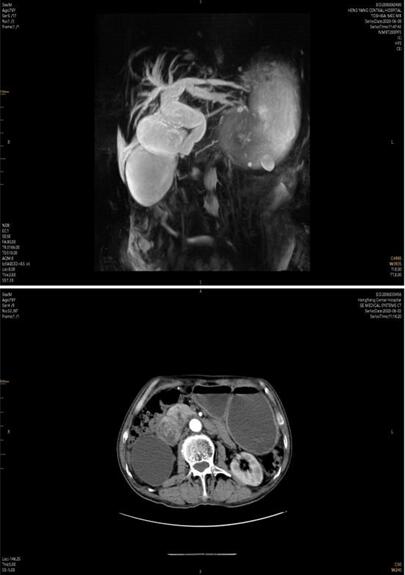

患者家屬經(jīng)多方打聽,赴我院胃腸外科會診。譚曙光主任及賀賽奇副主任閱外院腹部CT片,考慮十二指腸惡性腫瘤合并梗阻可能性大,唯有手術(shù)治療方為解決患者病癥最好方式??紤]患者高齡,全身營養(yǎng)狀況差,脫水及貧血嚴(yán)重,予積極補(bǔ)液、維持水電解質(zhì)平衡、腸外營養(yǎng)支持及輸血治療同時,完善術(shù)前相關(guān)輔助檢查。上腹部增強(qiáng)MRI+MRCP檢查提示:十二指腸水平段腫瘤,侵犯膽管下段、胰頭、橫結(jié)腸系膜,并周圍多發(fā)淋巴結(jié)腫大。十二指腸鏡下活檢病理:十二指腸粘膜慢性炎。

術(shù)前3天,患者并發(fā)上消化道出血,考慮腫瘤病變進(jìn)展,侵及十二指腸局部血管出血,病情緊急,經(jīng)采取措施積極控制出血及輸血治療后,譚曙光主任醫(yī)師主持科內(nèi)疑難病例討論:患者為十二指腸腫瘤來源可能性大,瘤體大,分期晚,合并消化道梗阻及出血,手術(shù)指征明確及迫切。腫瘤侵犯膽管、胰頭、橫結(jié)腸系膜及血管,經(jīng)典胰十二指腸切除即Whipple手術(shù)切除困難,需經(jīng)十二指腸及胰腺后方血管入路(經(jīng)腸系膜上動脈及腹主動脈、下腔靜脈表面)進(jìn)行手術(shù),難度極大,風(fēng)險極高,隨時可能出現(xiàn)大血管破裂大出血并危及生命,為減輕患者創(chuàng)傷、術(shù)后恢復(fù)快,腹腔鏡手術(shù)操作更是難上加難。